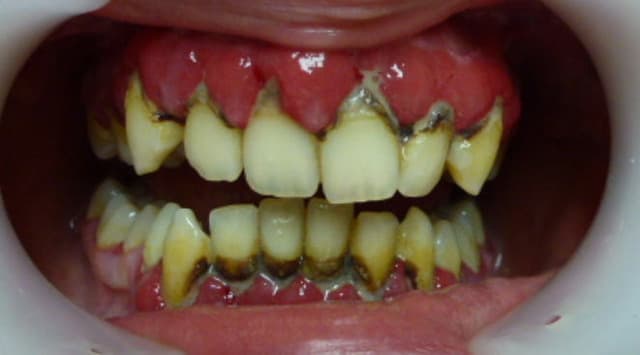

J'ai gagné le concours!!!

Photo2 e7wjad - Eugenol

Photo2 xubvrb - Eugenol

Images jm2g2g - Eugenol